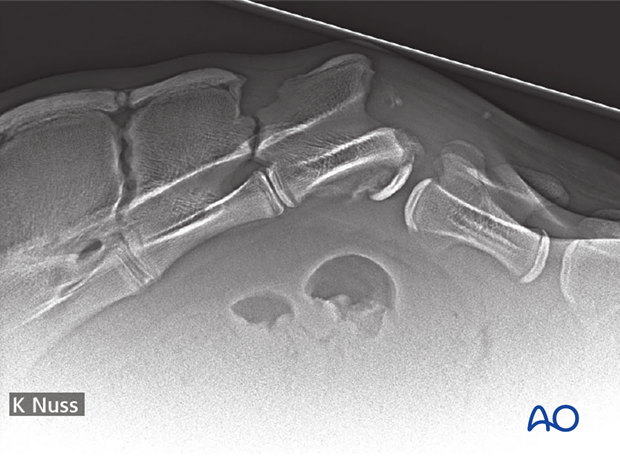

A coccygeal luxation and avulsion fracture is shown.